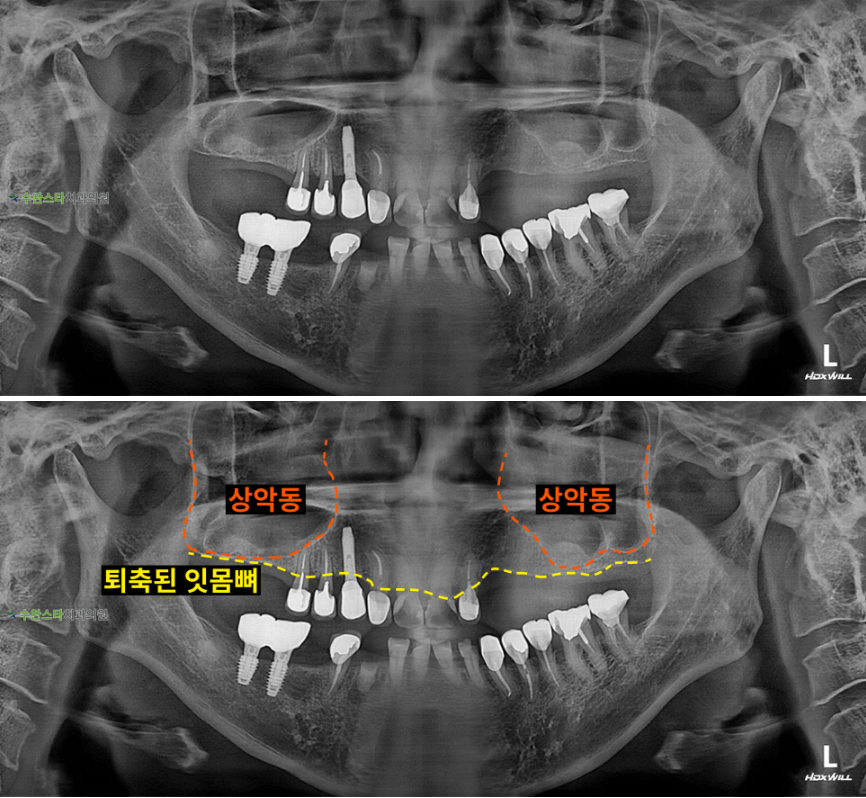

내원 시 파노라마

처음 내원 시 파노라마, 50대 여성 (2025. 11 촬영)

내원 시 파노라마 사진입니다.

살릴 수 있는 자연치아를

최대한 보존하고

발치 후 뼈 이식과

임플란트를 진행하기로

했습니다.

잇몸뼈가 부족한 경우에는

상악동 거상술을 통한

전체적으로 뼈이식이 필요합니다.